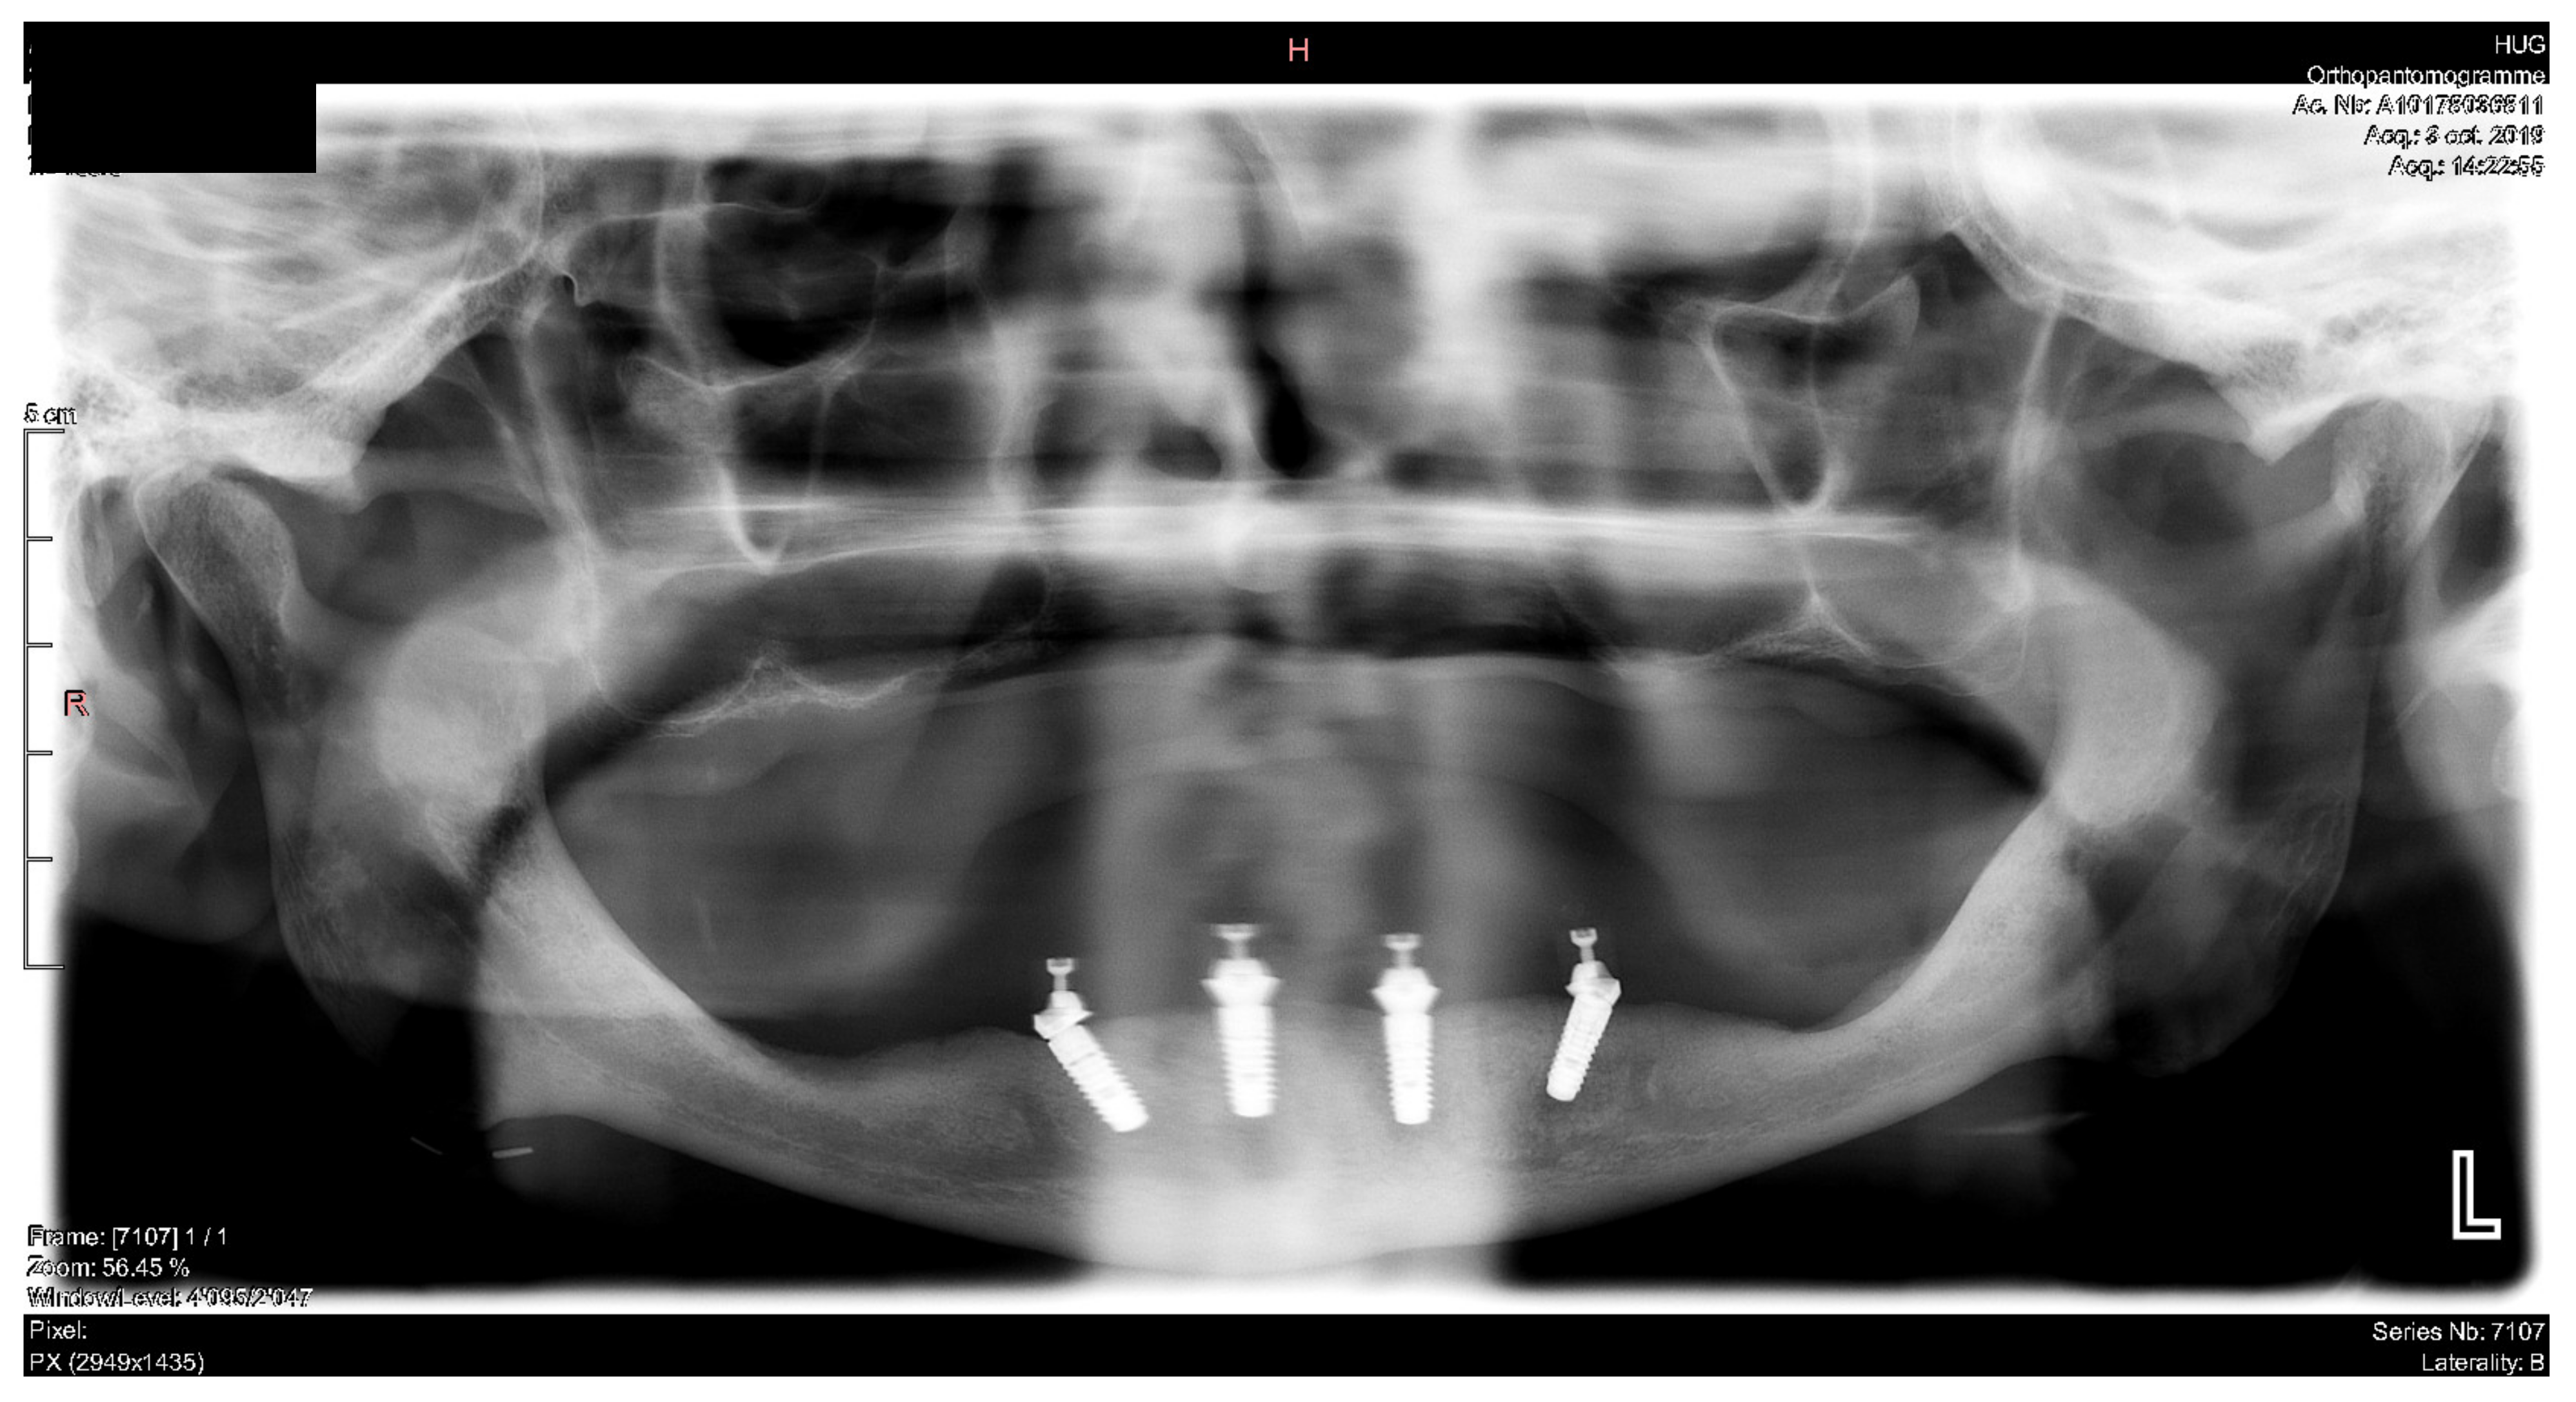

Smile frontal close-up views.

Figure 29.

Panoramic radiograph showing the dental implants in place.

Figure 38.